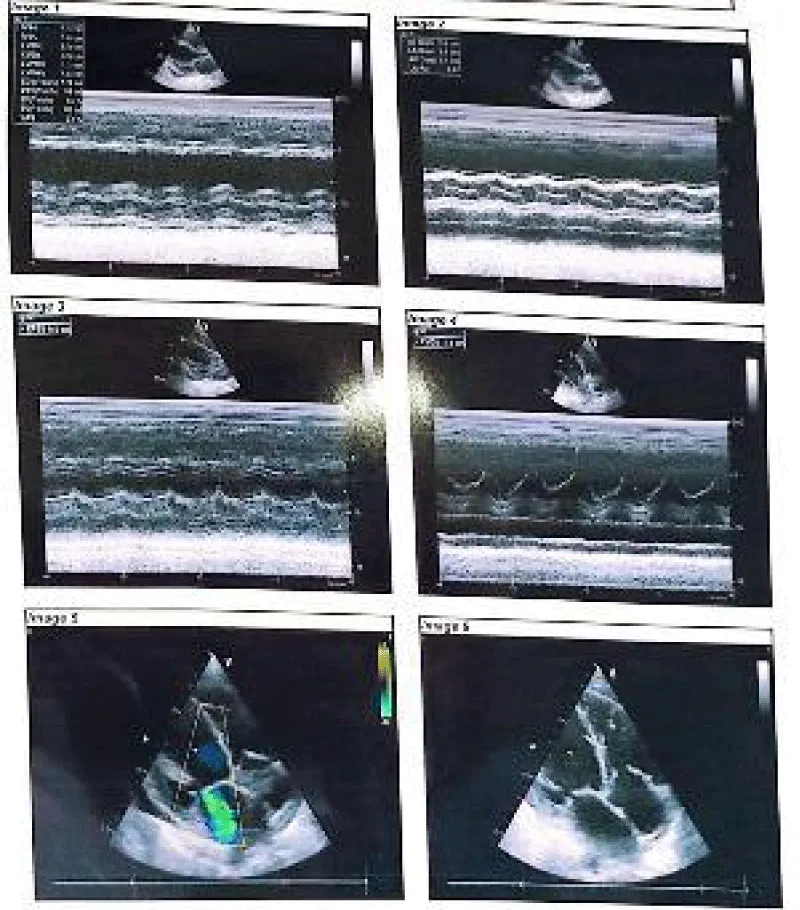

Her complete blood count, lipase, CRP, troponin, electrolytes, creatinine, calcium, magnesium, alkaline phosphatase, and urine routine microscopic examinations were unremarkable. Her bicarbonate level was 17.0 mmol/L and revealed an anion gap of 32.34. The lipid profile was abnormal for triglycerides of 984 mg/dL. Chest x-ray showed cardiomegaly (Figure 2). An echocardiogram showed dilated cardiomyopathy, mild MR, TR, and LV systolic dysfunction-ejection fraction (EF) of 45% (Figure 3). The patient was shifted to the general ward after 2 days upon stabilization. A diagnosis of acute severe pancreatitis was considered initially based on the clinical presentation with peripartum cardiomyopathy as the differential diagnosis. Based on her clinical signs, symptoms, and results of additional tests, the diagnosis of peripartum cardiomyopathy was made. After a consultation with the cardiology department, she was initiated on diuretics, ACEi, Beta Blockers, iron supplementation, empagliflozin, thiamine, and statin. Careful counseling was done regarding contraception and future pregnancies. She was advised to follow up one month later.

Download Image

Figure 3: Left ventricular cavity dilated, global hypokinesia with mild TR and MR is noted.